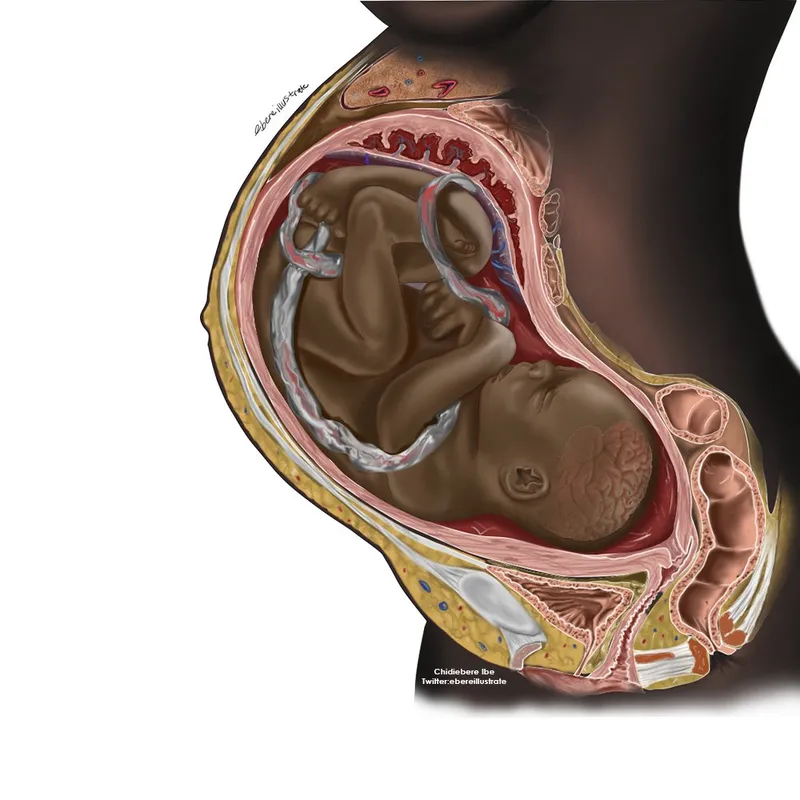

The image of a black fetus inside a black woman’s womb; which was illustrated by Chidiebere Ibe and posted on 24th November 2021; went viral and also opened up conversations regarding the underrepresentation of black people in medical illustrations. On Twitter, the image was liked over 8,000 times and retweeted over 2,500 times. Also, On Instagram, the image was liked over 100,000 times. One twitter user shared the photo and wrote, “I’ve literally never seen a black fetus illustrated, ever.” And now, for his noble efforts; the young medical student and aspiring neurosurgeon is set to have his illustrations published.

Since his illustrations went Viral, Ibe, who is the creative director at the Association of Future African Neurosurgeons, and a student of medicine in Ukraine; has been invited to have his illustrations published in the second edition of a handbook; that is meant to show medical conditions that appear on Black skin.

“Mind the Gap: A clinical handbook of signs and symptoms in Black and Brown Skin,” was first published in 2020. Co-author Malone Mukwende, a medical student in London, wrote over email that “Chidiebere’s work … unearths some of the biases that exist in medicine in plain sight that we may not be aware of. Representation in healthcare is imperative to ensure that we do not allow implicit biases to cultivate in our heads.”

Despite making up an eighth of the world’s population, Africa accounted for less than 1% of global research output between 2012 and 2016. Even in Nigeria, White skin images dominate the medical literature, says Ibe. His goal is to help remedy that by setting up a network of African medical illustrators.

Ibe plans to become a pediatric neurosurgeon and is also working on a textbook on birth defects in children; which will be illustrated with Black skin images.

Malone Mukwende, a Zimbabwe-born medical student in London and co-author of the handbook; thinks that they can create a “blueprint” of what a diverse medical textbook looks like, according to CNN.

Mukwende, wrote the first edition of Mind the Gap: A Handbook of Clinical Signs in Black and Brown Skin, in 2020 to illustrate how medical conditions appear on darker skin.